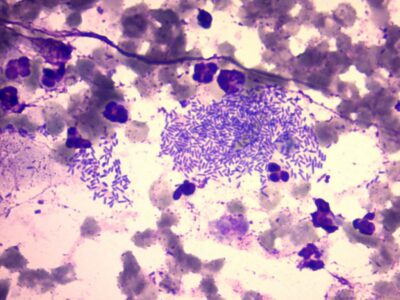

bacteria - skin cytology

bacteria Simonsiella

bacteria Simonsiella -